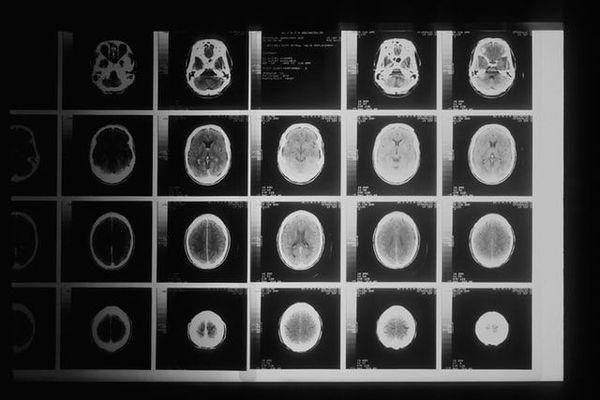

Segmenting brain lesions and 3D medical images

When somebody has a stroke, the most common type of stroke is an ischemic stroke. That means there’s a blood clot somewhere in a brain vessel that services an area of the brain. It's reducing blood flow to that area.

Problem: tissue death

If that blood flow is not restored, then this is going to result in tissue death. When someone has a stroke, and they go to the hospital, they'll either get a CT scan, or they'll get an MRI scan done. The goal of this work is to be able to read that scan and then automatically segment or automatically put contours around where the ischemic stroke has occurred.

This can be used for stroke treatment decisions. Now, if you look at an MRI scan, it's quite obvious to tell where the ischemic stroke lesion is. There are these white splotches that indicate this. It's much more difficult to get this information by looking at a CT scan.

However, CT has advantages over MRI, it's much cheaper, it's faster, and it's much more readily available than MRI.